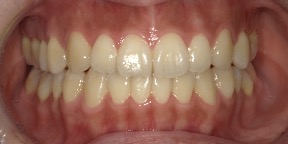

33歳女性のビフォーアフター

| 診断 | 空隙 |

| 治療方針 | 治療方針:前歯の咬合関係改善と空隙閉鎖を主な目的にて主にIPR(歯と歯の間をわずかに削合してスペースを獲得する方法)を組み込んだ動的矯正治療を行い、空隙、前歯咬合を改善後、保定を行う。臼歯部の咬合関係はプランの都合上維持することとした。 |

| 治療費 ※ | 67万8千円(診断、型取り、矯正中のメンテナンス、保定装置を含む料金) |

| 治療期間 | 6か月 |

| リスク | 1日20時間以上マウスピースを使用できない場合、歯が動かなかったり、想定しない誤差により不完全に終わる可能性がある。装着時や食事時に痛みを伴う。歯肉退縮や虫歯になるおそれがある。また、指導通りに装着できていない場合や適切なブラッシングが出来ていないとそのリスクが高くなる。歯根が短くなることがある。ごくまれに歯の神経が損傷してしまうことがある。過去にぶつけたり深い虫歯治療をしたことがあるとそのリスクはやや高くなる。矯正後には保定装置が必要。適切な使用ができない場合、後戻りの原因となる。将来的に歯並びが動いて再矯正が必要な場合がある。親知らずが正常に生えていない場合、その可能性がやや高くなる。 |